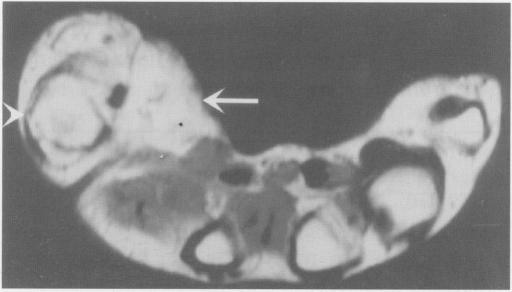

MR imaging of macrodystrophia lipomatosa.

Ulster Med J. 2005 May;74(1):47-50.